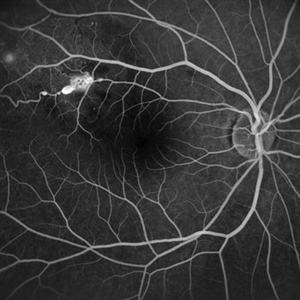

Central Artery Occlusion with Cilio Retinal Artery Sparing Central Artery Occlusion with Cilio Retinal Artery SparingAug 6 2023 by Anjana Mirajkar, MS Ophthalmology Wide field view of FA (Early phase) of a 42 year old male in a case of central artery occlusion with cilio retinal artery sparing showing delayed arterial filling with choroidal filling Photographer: Dr. Anjana Mirajkar -Retina Foundation, Ahmedabad Condition/keywords: central retinal artery occlusion

Central Artery Occlusion with Cilio Retinal Artery Sparing Central Artery Occlusion with Cilio Retinal Artery SparingAug 6 2023 by Anjana Mirajkar, MS Ophthalmology Wide field view of FA (Late phase) of a 42 year old male in a case of central artery occlusion with cilio retinal artery sparing showing delayed arterial filling with choroidal filling Photographer: Dr. Anjana Mirajkar -Retina Foundation, Ahmedabad Condition/keywords: central retinal artery occlusion (CRAO)